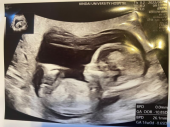

娘 5ヶ月

娘が妊婦健診で帰って来た。もうすぐ5ヶ月。安定期に入り、少し安堵。わたしにとって3人目の孫。超音波画像では、ようやくヒトの形になった。

今はこんなにハッキリ写るんですね 出産予定は11月かな?楽しみですね

予定は12月中旬。クリスマス前ですね。